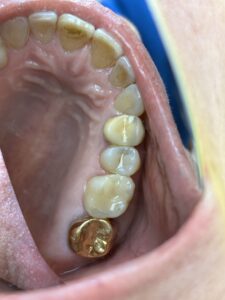

セラミックインレーやジルコニアクラウンもおすすめです。これらは自費ですが。

ジルコニアは頑丈ですね。